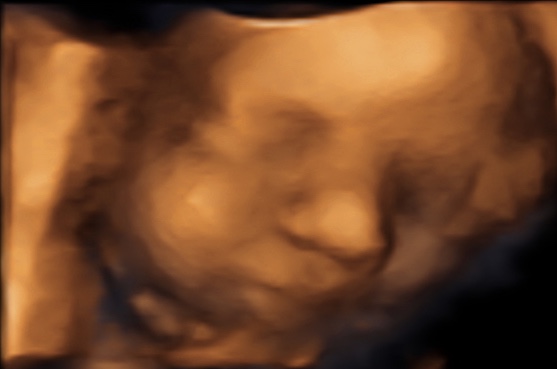

39 weken

Een echo na 39 weken.